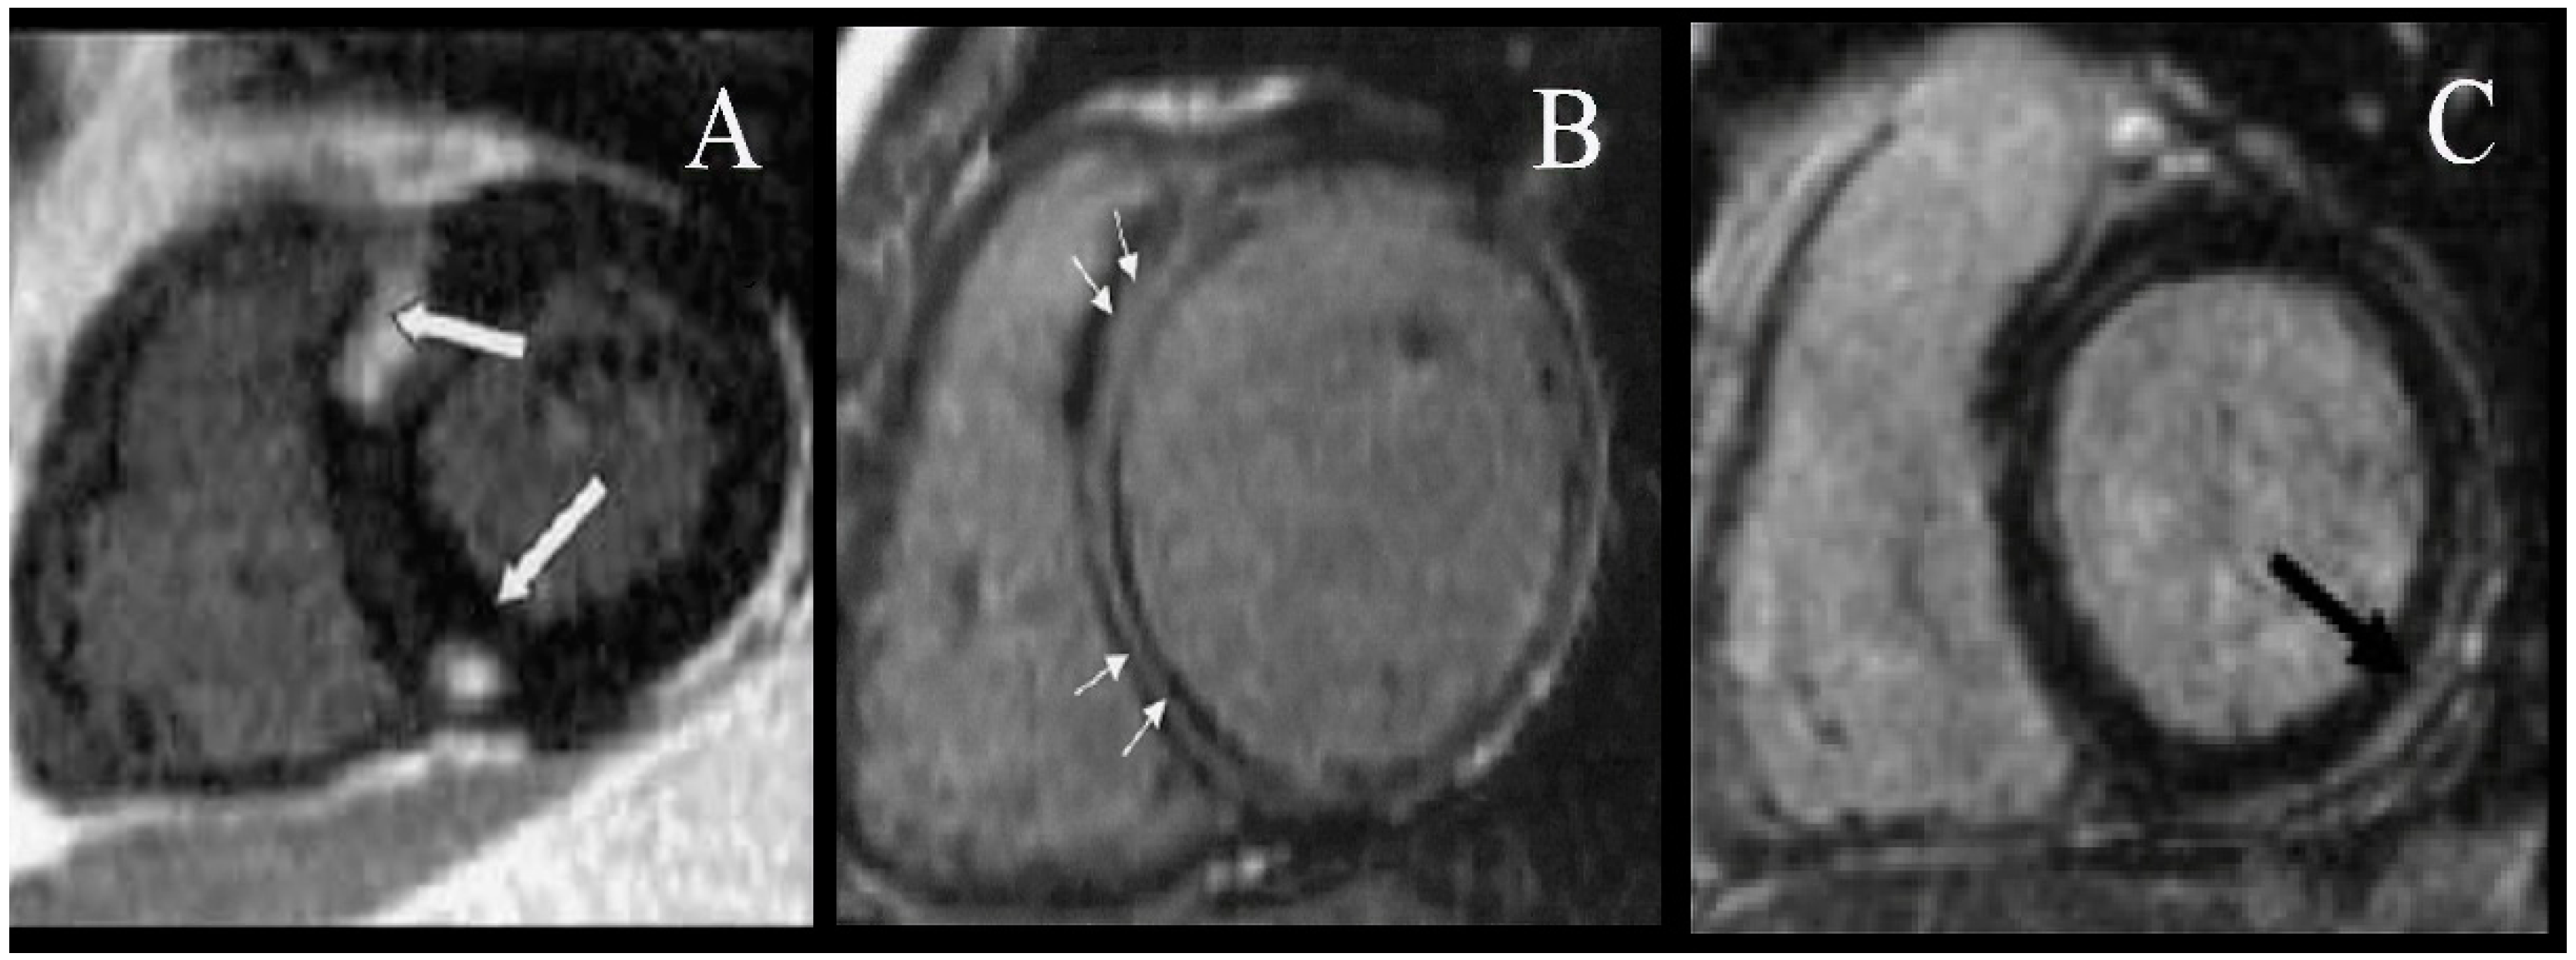

- Holmström, M.; Kivistö, S.; Heliö, T.; Jurkko, R.; Kaartinen, M.; Antila, M.; Reissell, E.; Kuusisto, J.; Kärkkäinen, S.; Peuhkurinen, K.; et al. Late gadolinium enhanced cardiovascular magnetic resonance of lamin A/C gene mutation related dilated cardiomyopathy. J. Cardiovasc. Magn. Reson. 2011, 13, 30. [Google Scholar] [CrossRef] [PubMed] [Green Version]

- Gräni, C.; Eichhorn, C.; Bière, L.; Murthy, V.L.; Agarwal, V.; Kaneko, K.; Cuddy, S.; Aghayev, A.; Steigner, M.; Blankstein, R.; et al. Prognostic value of cardiac magnetic resonance tissue characterization in risk stratifying patients with suspected myocarditis. J. Am. Coll. Cardiol. 2017, 70, 1964–1976. [Google Scholar] [CrossRef] [PubMed]

- Aquaro, G.D.; Perfetti, M.; Camastra, G.; Monti, L.; Dellegrottaglie, S.; Moro, C.; Pepe, A.; Todiere, G.; Lanzillo, C.; Scatteia, A.; et al. Faculty Opinions recommendation of Cardiac MR with late gadolinium enhancement in acute myocarditis with preserved systolic function: ITAMY study. J. Am. Coll. Cardiol. 2018, 70. [Google Scholar] [CrossRef]

- Fallah-Rad, N.; Lytwyn, M.; Fang, T.; Kirkpatrick, I.; Jassal, D.S. Delayed contrast enhancement cardiac magnetic resonance imaging in trastuzumab induced cardiomyopathy. J. Cardiovasc. Magn. Reson. 2008, 10, 5. [Google Scholar] [CrossRef] [PubMed] [Green Version]

- Becker, M.A.; Cornel, J.H.; Van De Ven, P.M.; Van Rossum, A.C.; Allaart, C.P.; Germans, T. The prognostic value of late gadolinium-enhanced cardiac magnetic resonance imaging in nonischemic dilated cardiomyopathy: A Review and Meta-Analysis. JACC Cardiovasc. Imaging 2018, 11, 1274–1284. [Google Scholar] [CrossRef]

- Fallah-Rad, N.; Walker, J.; Wassef, A.; Lytwyn, M.; Bohonis, S.; Fang, T.; Tian, G.; Kirkpatrick, I.D.; Singal, P.K.; Krahn, M.; et al. The utility of cardiac biomarkers, tissue velocity and strain imaging, and cardiac magnetic resonance imaging in predicting early left ventricular dysfunction in patients with human epidermal growth factor receptor II–positive breast cancer treated with adjuvant trastuzumab therapy. J. Am. Coll. Cardiol. 2011, 57, 2263–2270. [Google Scholar] [CrossRef]

- Bernaba, B.N.; Chan, J.B.; Lai, C.K.; Fishbein, M.C. Pathology of late-onset anthracycline cardiomyopathy. Cardiovasc. Pathol. 2010, 19, 308–311. [Google Scholar] [CrossRef]

- Tham, E.B.; Haykowsky, M.J.; Chow, K.; Spavor, M.; Kaneko, S.; Khoo, N.S.; Pagano, J.J.; Mackie, A.S.; Thompson, R. Diffuse myocardial fibrosis by T1-mapping in children with subclinical anthracycline cardiotoxicity: Relationship to exercise capacity, cumulative dose and remodeling. J. Cardiovasc. Magn. Reson. 2013, 15, 48. [Google Scholar] [CrossRef] [Green Version]

- Neilan, T.G.; Coelho-Filho, O.R.; Shah, R.V.; Feng, J.; Pena-Herrera, D.; Mandry, D.; Pierre-Mongeon, F.; Heydari, B.; Francis, S.A.; Moslehi, J.; et al. Myocardial extracellular volume by cardiac magnetic resonance imaging in patients treated with anthracycline-based chemotherapy. Am. J. Cardiol. 2012, 111, 717–722. [Google Scholar] [CrossRef] [Green Version]

- Galán-Arriola, C.; Lobo, M.; Vílchez-Tschischke, J.P.; López, G.J.; De Molina-Iracheta, A.; Perez-Martinez, C.; Aguero, J.; Fernández-Jiménez, R.; Martín-García, A.; Oliver, E.; et al. Serial magnetic resonance imaging to identify early stages of anthracycline-induced cardiotoxicity. J. Am. Coll. Cardiol. 2019, 73, 779–791. [Google Scholar] [CrossRef]